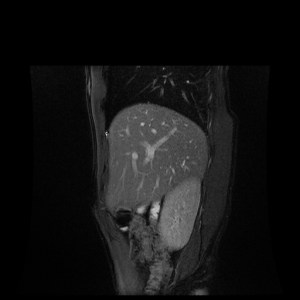

test_MR_NO_20180123_002